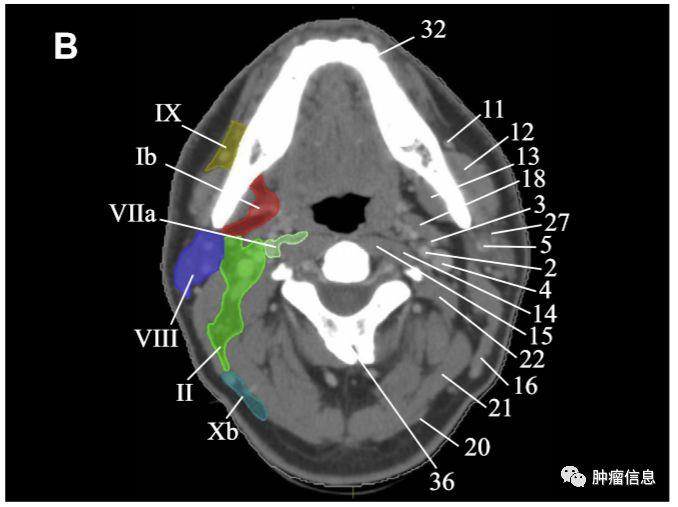

RTOG2013年头颈部淋巴结分区勾画图谱:

Ia:颏下淋巴组Ib:颌下淋巴组II:上颈淋巴组III :中颈淋巴组IVa:下颈淋巴组IVb:锁骨上内侧组V:颈后三角淋巴组Va:上颈后三角淋巴组Vb:下颈后三角淋巴组Vc:锁骨上外侧组VI:颈前淋巴组VIa:颈前淋巴结VIb:喉前、气管前、气管旁淋巴结VII:椎前淋巴组VIIa:咽后淋巴结VIIb:茎突后淋巴结VIII:腮腺淋巴组IX:面颊淋巴组X:颅底后组Xa:耳后、耳下淋巴结Xb:枕淋巴结见下图: